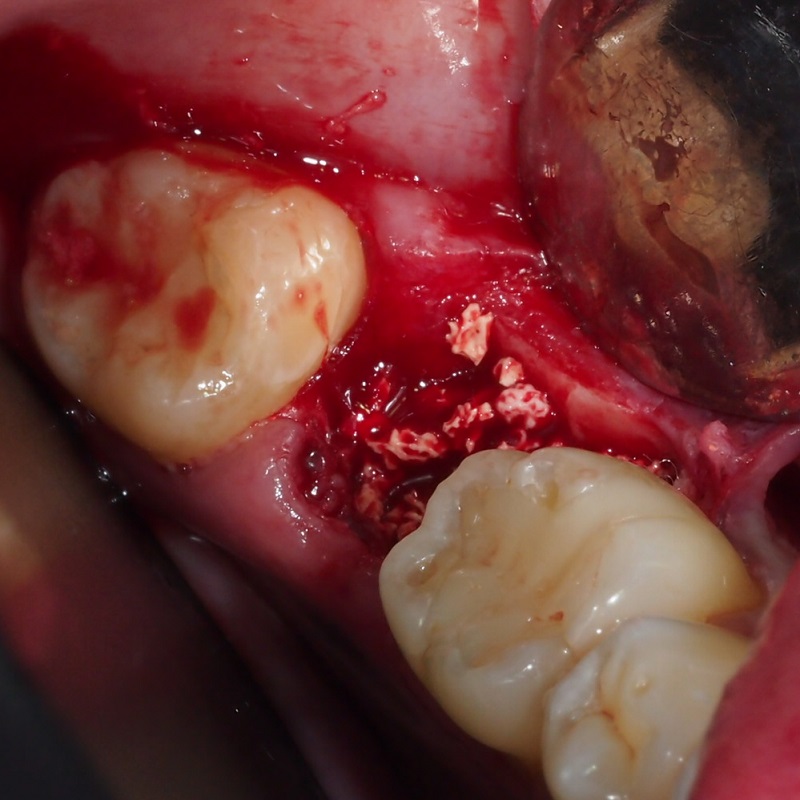

Extracción Con Preservación de Alvéolo

La extracción con preservación alvéolo es el mejor inicio para la colocación de un implante dental, el alveolo o hueco dejado después de la extracción se rellena con material de regeneración evitando que este colapse y por ende que se muevan los dientes adyacentes, evita también la absorción de hueso post extracción aumentando la tasa de éxito para la colocación de un implante.

• Aplicación de anestesia local

• Extracción atraumatica del órgano dental

• Preparación del alvéolo

• Colocación de material de regeneración

• Sutura del área intervenida